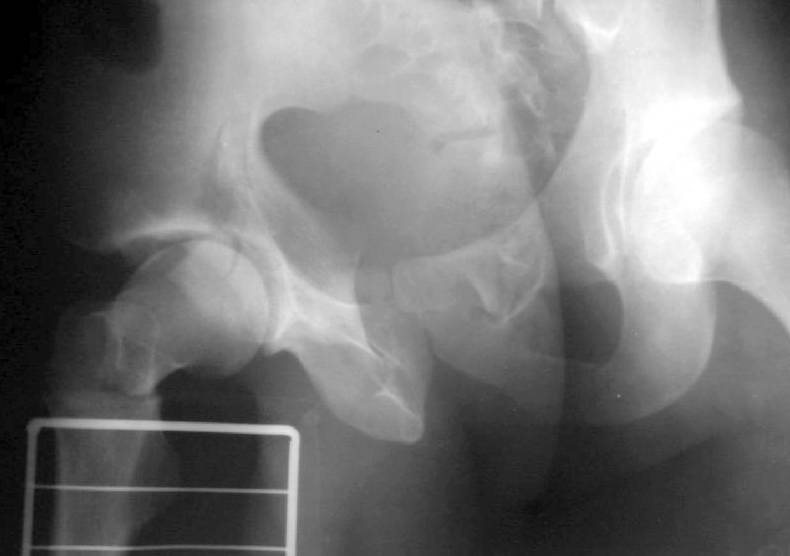

OK, we just fixed all fractures as the patient shows no infection signs. Posterior column was perQ (nice abbreviation) fixed by a screw and a wire, rami - by screws. Then closed locked nailing was performed (i placed a single screw at the upper level - is it commonly acceptable?) and "miss a nail" three cancellous screws to the neck (at the moment we have no more available implants suitable for this lesion like gamma nail etc, so the choice was easy :-). The external fixator left in place as a "local sceletal traction" for a couple of weeks. Acetabular, femoral shaft and neck images attached.